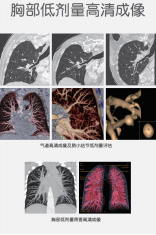

高清病例展示图:

01

ct什么牌子的好【喜讯】瑶医医院影像科大型CT设备顺利开机并投入使用_https://www.jmylbn.com_新闻资讯_第7张

02

ct什么牌子的好【喜讯】瑶医医院影像科大型CT设备顺利开机并投入使用_https://www.jmylbn.com_新闻资讯_第8张

03

ct什么牌子的好【喜讯】瑶医医院影像科大型CT设备顺利开机并投入使用_https://www.jmylbn.com_新闻资讯_第9张